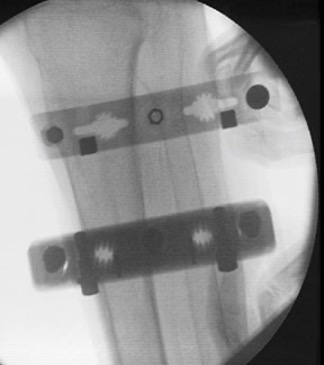

Radiolucent

Plastic radiolucent photoarticles are transparent to short wavelength radiation and appear nearly invisible on x-rays or during fluoroscopy procedures. Inclusion of additional additives into long fiber composites can render molded articles radiopaque for medical diagnostic procedures. Long glass fiber composites are safe to use in proximity with magnetic resonance imaging (MRI) and computed tomography (CT or CAT) scan diagnostic equipment because of their non-magnetic and electrically insulative characteristics.